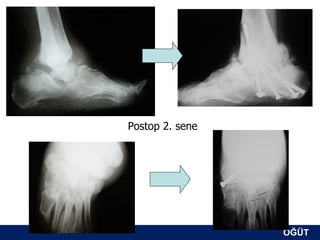

Postop 2. sene